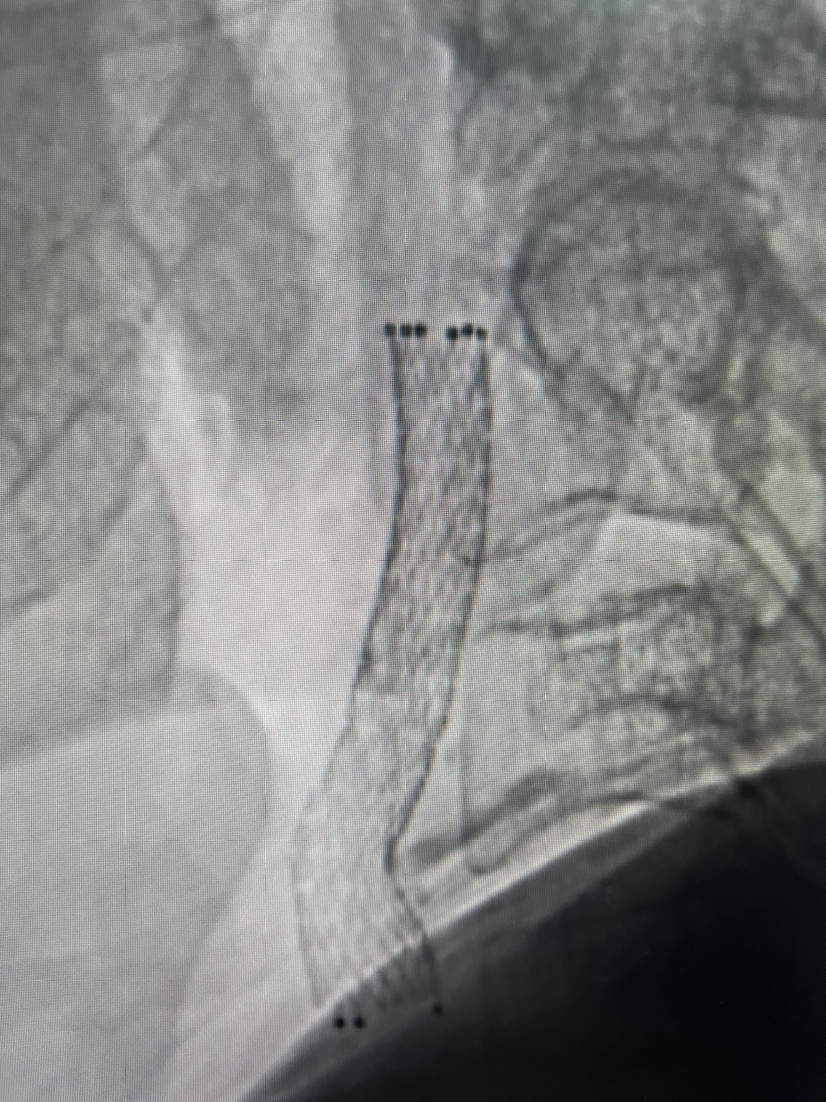

5mmx30mm球囊扩张